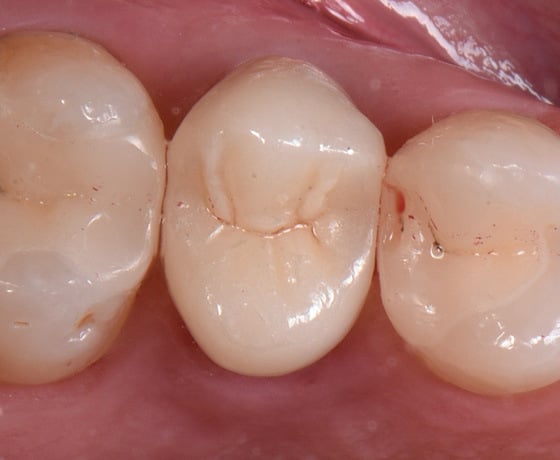

Risultato dopo la cementazione.